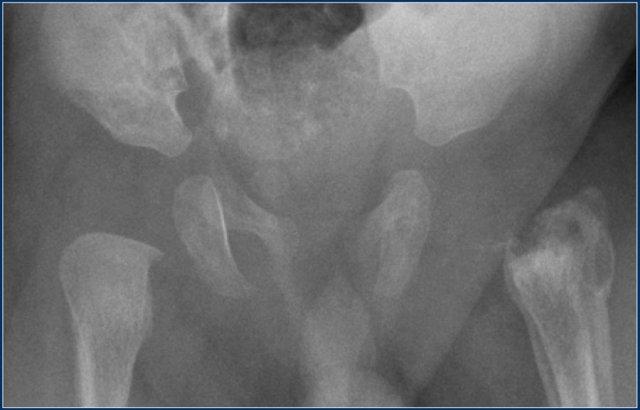

Trượt đầu xương đùi ở một bé trai mười ba tuổi. Phim X-quang tư thế thẳng cho thấy đầu xương hơi rộng, nhưng dấu hiệu này dễ bị bỏ sót. Tư thế chụp nghiêng kiểu ếch cho thấy trượt đầu xương đùi trái ra sau-trong.

Trượt Đầu Xương Đùi

Trượt đầu xương đùi (SCFE) hay còn gọi là tiêu xương đùi đầu là gãy xương Salter-Harris type I vô căn của đầu xương đùi gần.

Bệnh gặp nhiều hơn ở trẻ trai và trẻ béo phì. Độ tuổi biểu hiện điển hình là từ 12 đến 15 tuổi.

SCFE có thể xảy ra hai bên trong tới một phần ba số trường hợp.

Đầu xương trượt ra sau, và ở mức độ ít hơn là vào trong.

Do đó, dấu hiệu này được đánh giá tốt nhất trên tư thế chụp nghiêng kiểu ếch.

SCFE được điều trị bằng cố định phẫu thuật để ngăn ngừa trượt thêm.

Hoại tử vô mạch đầu xương đùi là một biến chứng tiềm ẩn.